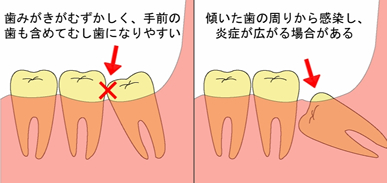

「親知らず」ってどういうときに抜くの |

![]() 親知らずの抜歯などの口腔外科

親知らずの抜歯などの口腔外科